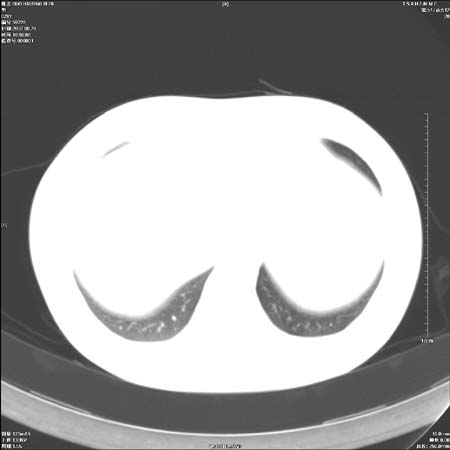

首先这个病例应该加薄层面扫描-可以很好显示支气管与肿块的情况。

鉴别:中央型肺癌-肿块那么明显一般合并节段肺不张或阻塞性炎症。

本例肿块边缘外侧可见左上叶各段支气管。

左侧肺门区见一块状病灶可见分叶,纵隔内及左肺门见肿大淋巴结,应该是周围型肺癌而不是中心型肺癌,原因有以下2点,1未见阻塞肺气肿和阻塞性炎症,这么大肿块如果是中心型肺癌就是未分化型或小细胞型肺癌不出现阻塞性肺不张也应该有阻塞炎症或阻塞性肺气肿,2如果是中心型肺癌临床出现最早的症状是咳嗽(此时可无任何异常影象),而此人这么大肿块只有背部隐痛是体检才发现无法解释.

直接下肺癌诊断还太早,病灶较大,估计5cm以上,但阻塞性改变及对临近纵隔及支气管侵犯不明显,密度较均匀,弓旁见一单个淋巴结,需要排除炎症性肿块及腺瘤,平滑肌瘤等。